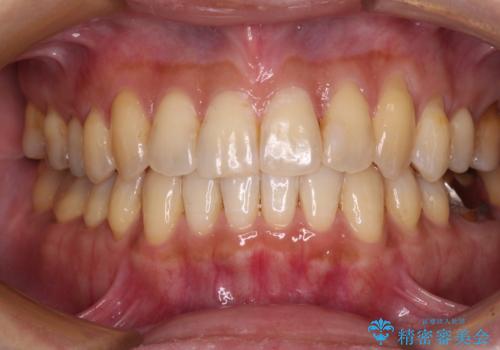

- 前歯のクロスバイトが気になり、インビザラインによる矯正治療を希望して来院された患者様です。

上顎側切歯(上の真ん中から2番目の歯)が舌側転位している場合、インビザラインでは仕上げきれないことが多く、更には無理して動かそうとすると歯髄壊死を起こすリスクが高いと言われています。

インビザラインで歯列を移動する前に、上顎前歯をワイヤー矯正で整え、その後上下歯列をインビザラインにて矯正治療を行うこととしました。

舌側転位している側切歯特有の、切縁の位置が不揃いであったり、根元が内側に引っ込んだ状態であったりという、インビザライン独特の仕上がりになることなく、きれいに整った歯列とすることができました。